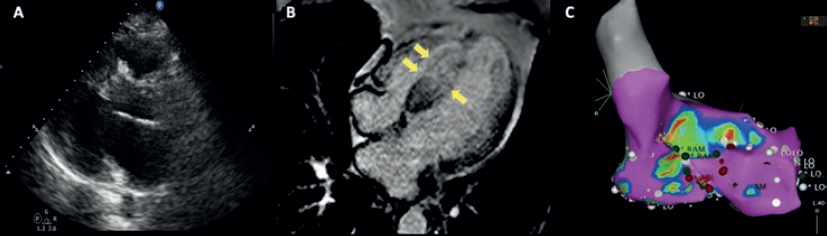

This is the case of a 51-year old male without a past medical history. One month before his admission he experienced fast heart palpitations associated with diaphoresis, nausea and vomit. Both the electrocardiogram and the Holter monitor showed recurring episodes of monomorphic ventricular tachycardia (figure 1). The physical examination confirmed the presence of an aortic ejection murmur exacerbated when performing the Valsalva maneuver. The transthoracic echocardiography showed obstructive asymmetric septal hypertrophy with a 32-mm maximum septal diameter (figure 2A), a 65-mmHg gradient in the left ventricular outflow tract, and systolic anterior motion of the mitral valve with moderate regurgitation. The cardiovascular magnetic resonance imaging confirmed the presence of extensive myocardial fibrosis as a risk factor of sudden death (figure 2B and video 1 of the supplementary data). Amiodarone and propranolol were prescribed, and an automatic defibrillator was implanted as a secondary prevention measure. The patient was readmitted to the hospital 4 months later with signs of electrical storm with multiple discharges provided by the device implanted. Deep sedation, mechanical ventilation, and hemodynamic support were administered, and the stellate ganglion was blocked. However, the patient progression was poor with persistent episodes of ventricular tachycardia that triggered the mapping of cardiac electrophysiology using the CARTO 3 system (Biosense Webster, Israel). The ablation of a septal macroreentrant circuit of the left ventricle associated with the clinical ventricular tachycardia was unsuccessful (figure 2C).

Figure 2. A: transthoracic echocardiography. Interventricular septum with a 32 mm diameter. B: magnetic resonance imaging showing late contrast (arrows). C: mapping of cardiac electrophysiology and ablation attempt of the septal macroreentrant. LO, voltage label; RAM, local electrogram label.